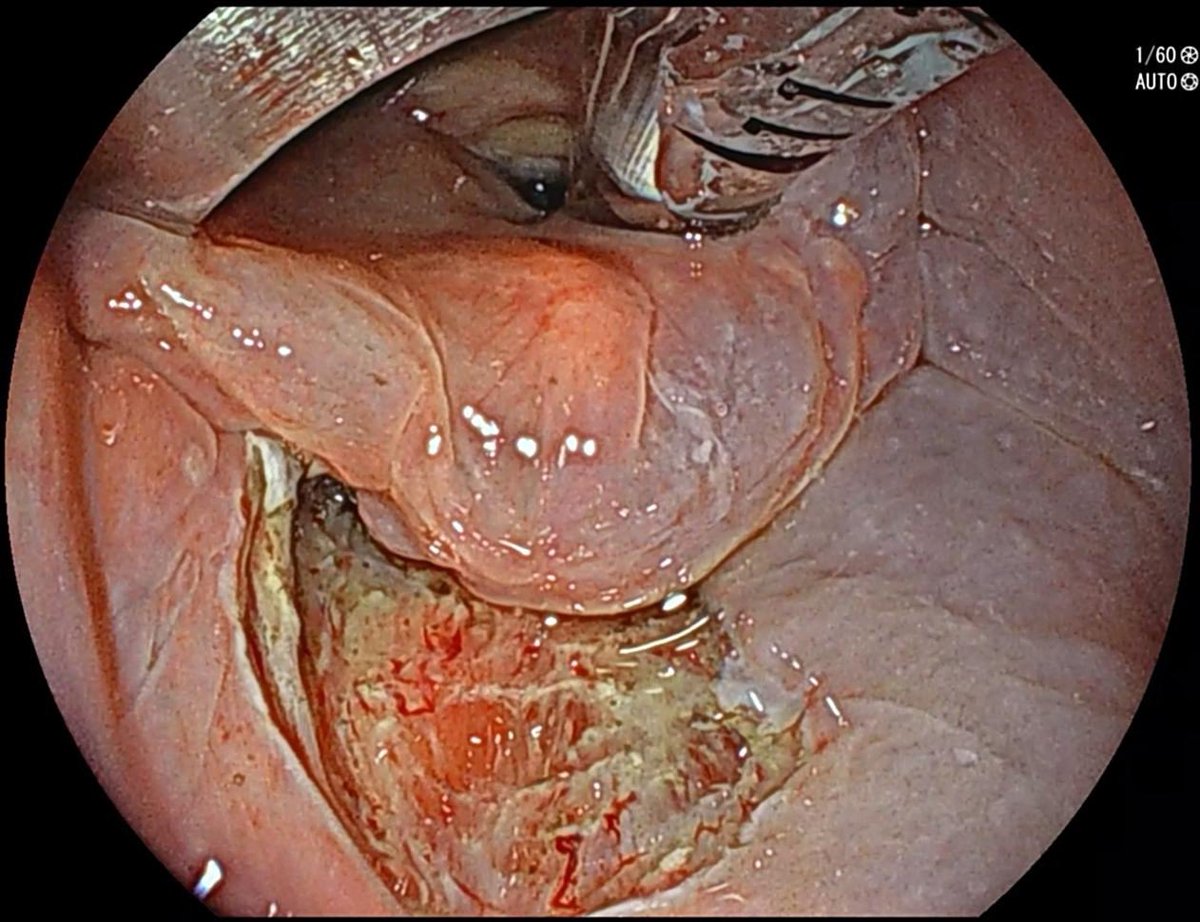

Delighted to share a MAJOR milestone in minimally invasive cancer treatment. We just completed the *first* Pharyngeal ESD in North America at @KingstonHSC . Huge thanks to the GI endoscopy team, @QueensuDOM, @SEAMOKingston for your endless support